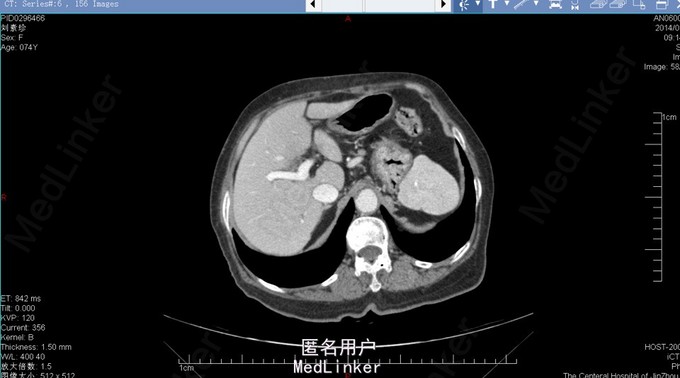

胆囊十二指肠瘘,结石性幽门梗阻

74岁女患,上腹部疼痛伴恶心呕吐3天。 3天前患者开始出现上腹部不适疼痛,同时伴有恶心、呕吐。呕吐物为胃内容物,餐后严重。患者在家自行消炎治疗,症状逐渐加重。患者为求进一步诊治来我院。 既往胆囊结石病史。

查体:上腹部压痛明显,伴反跳痛及肌紧张。 腹部ct:十二指肠内结石?(回忆部分)

胆囊十二指肠瘘,结石性幽门梗阻,腹膜炎。 给予患者胆囊切除+十二指肠修补局部引流?(记不太清)患者术后恢复还可以,顺利出院。

此病例为普外科轮转期间收集影像资料所得,病例内细致资料不全面,不能详尽分享。但此种病例少见,影像资料清晰,值得学习探讨。 欢迎普外专业同道探讨患者手术方式。让大家共同进步。